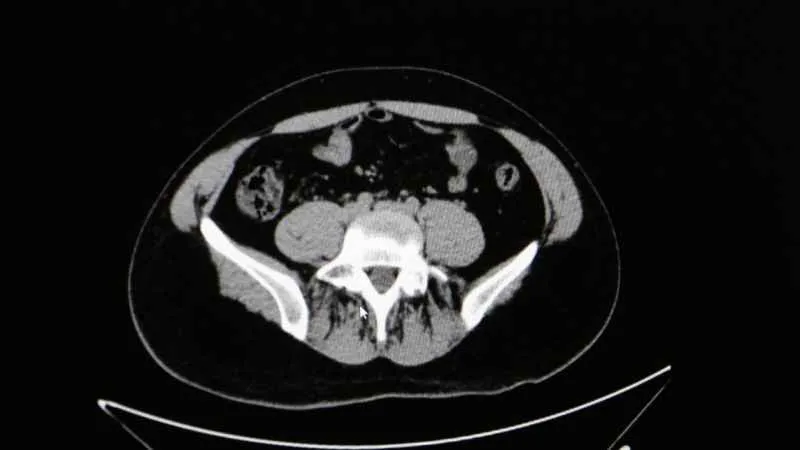

Diyarbakır Dicle Memorial Hastanesi’nde görev yapan Üroloji Uzmanı Op. Dr. Birgi Ercili “Sistit, aslında idrar torbası dediğimiz mesanenin iltihabıdır. Daha çok enfeksiyon sebepleriyle oluşur. Sistin daha çok sebebi idrar yoluna genital bölgeden ulaşan mikroorganizmalardır. Özellikle kadınlarda sistit dediğimiz durum çok fazla görülür. Çünkü kadınlarda üretra dediğimiz idrar yolu, erkeklere göre oldukça kısadır. Vajina ve anüse yakın olduğu için oradan gelen mikroorganizmaların idrar yolu aracılığıyla mesaneye ulaşması daha kolaydır. Kadınların yarısı hayatlarında muhakkak en az bir defa bu hastalığı geçirmektedir” ifadelerine yer verdi.

Sistitin sık görülen belirtilerinden idrar yanması ve az idrar yapma olduğunu ifade eden Ercili, “Sistit geliştiğinde özellikle idrarda yanma, sızı, sık sık ve az idrar yapma, damla damla idrar yapma, kasık ve alt karın bölgesinde ağrı, idrarda kan ve bulanık idrar görülebilir. Bazen de kadınlarda ilişki sonrası ağrı görülebilir. Genital hijyene çok dikkat edilmemesiyle, tuvalet temizliğini arkadan öne doğru yapılmasıyla mikropların idrar yoluna daha hızlı şekilde ulaşabildiğini görmekteyiz. Bunların dışında nemli çamaşırlarla beklemek, sık çamaşır değiştirmemek, az sıvı almak sistite sebep olabilmektedir. İlişki sonrasında da yine idrar yolunda tahriş meydana geldiği için sistit durumlarını görebilmekteyiz” diye konuştu.

“Hastanın şikayetlerini dinledikten sonra basit bir idrar tahliliyle sistit tanısını rahatlıkla koyabiliyoruz. Tedavisinde de genelde kısa süreli 5 gün kadar kullanılan ağızdan bir antibiyotik tedavisiyle rahatlıkla tedavi edebiliyoruz. Bunun yanında mutlaka bol sıvı almak da tedavinin önemli bir parçasını oluşturmaktadır.”